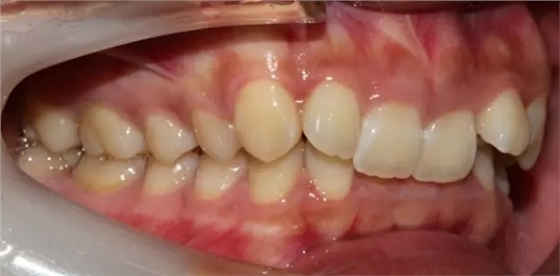

上下牙列擁擠,磨牙尖牙Ⅱ 類關(guān)系,3 度的深覆牙合,上頜中切牙伸長內(nèi)傾拔除上頜雙側(cè)的第一前磨牙,先粘上頜高轉(zhuǎn)矩的自鎖托槽排齊牙列,唇向開展上頜切牙,有一定的覆蓋,粘下頜標準轉(zhuǎn)矩托槽,上頜 1, 2 之間植入種植支抗壓入,同時后牙 5, 6 之間植入種植支抗內(nèi)收前牙,打開咬合關(guān)閉間隙。治療關(guān)鍵:前牙轉(zhuǎn)矩的控制第 1 個月 上頜粘上 Damon Q 高轉(zhuǎn)矩托槽,上 .014 熱激活 NiTi 絲。第 3 個月 上換 .014 x .025 熱激活 NiTi 絲。第 5 個月 上頜基本排齊,覆蓋增大,上換 .017 x .025 NiTi絲,下頜粘托槽,下 .014 熱激活 NiTi 絲。第 7 個月 上 .017 x .025 NiTi 絲加搖椅,下?lián)Q .014 x .025 熱激活 NiTi 絲第 9 個月 上頜換 .019 x .025 NiTi 絲加搖椅,下頜換 .017 x .025 NiTi 絲第 11 個月 下頜換 .019 x .025 加搖椅,上頜 1, 2 之間, 5, 6 之間植入種植釘,下頜出現(xiàn)散隙。第 13 個月 上頜換 .019 x .025ss 加搖椅,前牙種植釘用 Power Chain 壓低前牙(每側(cè) 100g),后牙種植釘關(guān)閉間隙(每側(cè) 150g),下?lián)Q .019 x .025ss,Power Chain 關(guān)閉間隙。第 19 個月 上頜前牙基本壓低到位去除前牙種植釘,繼續(xù)用關(guān)閉間隙,下頜散隙關(guān)閉。